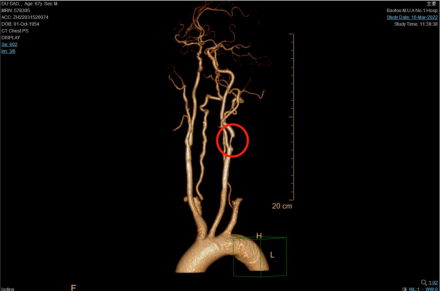

CTA提示杜大爷右侧颈动脉狭窄,狭窄率约为85%(重度狭窄)